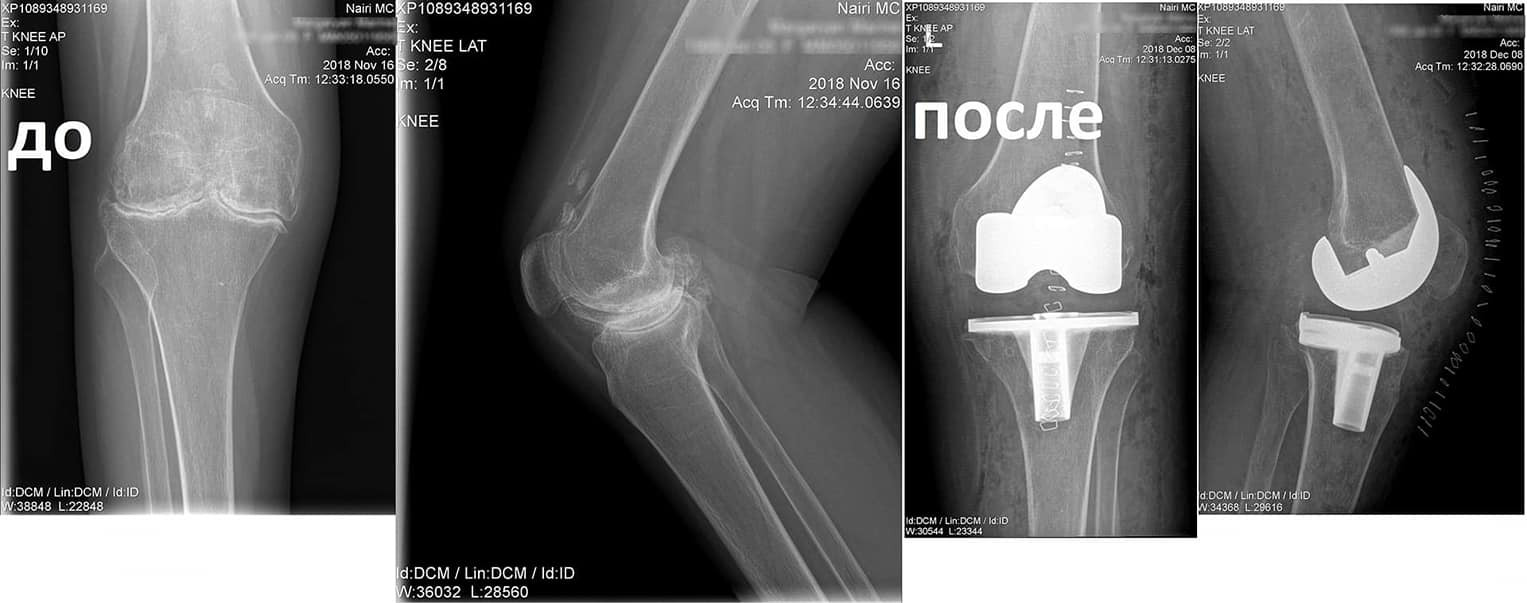

Կլինիկական դեպք. երկկողմանի գոնարթրոզ՝ ծնկահոդերի արթրոզ

Պացիենտը դիմել էր «Նաիրի» բժշկական կենտրոն` նստասալյակի օգնությամբ, ծանրագույն ցավերով, շարժումների խիստ սահմանափակումով:

Ծանրագույն պոլիարթրիտի հետևանքով առաջացել էր ծնկահոդերի արթրոզ։

Նման դեպքերում վիրահատույթունից առաջ պահանջվում է լրջագույն նախապատրաստում և հետվիրահատական հսկողություն:

Նախավիրահատական ընթացակարգից հետո իրականացվել է զույգ ծնկահոդերի փուլային էնդոպրոթեզավորում: Վիրահատությունից մի քանի ամիս անց պացիենտը չի ունեցել ցավեր, ազատ քայլել է և սկսել է ապրել լիարժեք կյանքով: